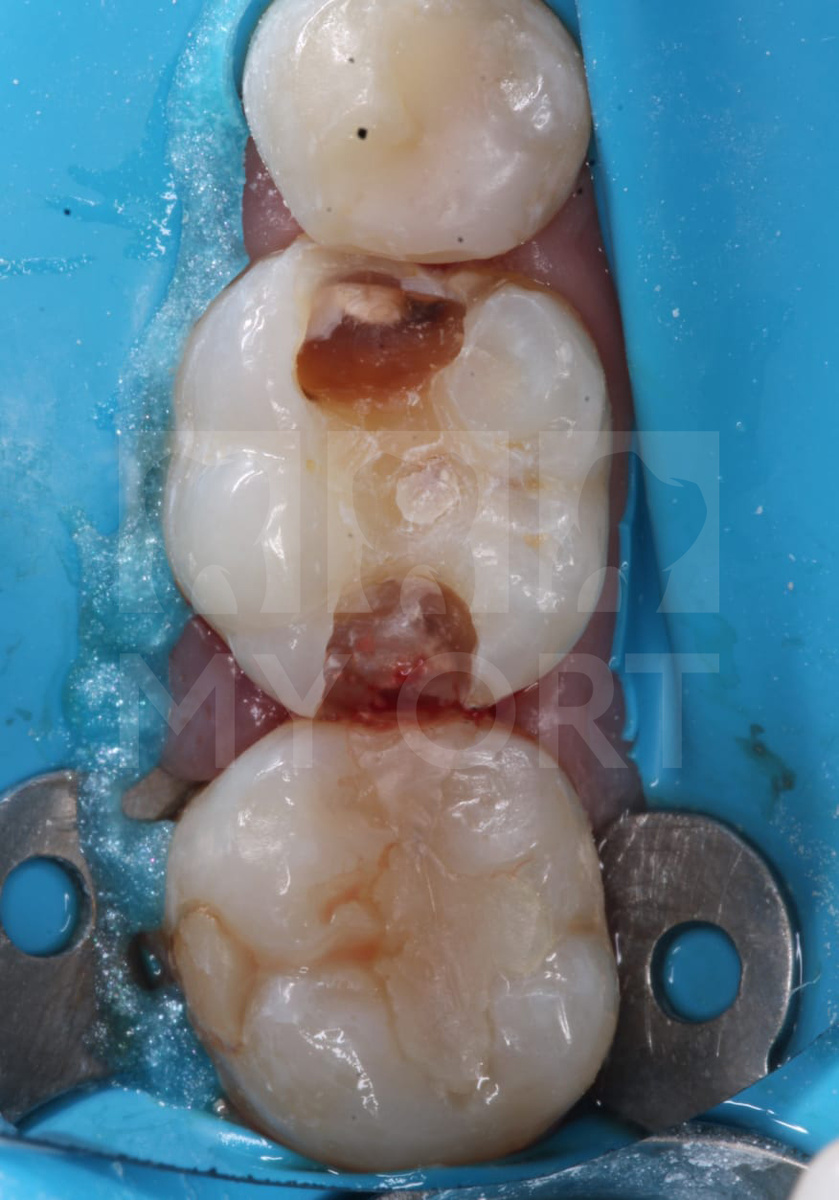

После изоляции зубов коффердамом приступила к препарированию пломбы 46 и 47 зубов. Видно, что под ними уже давно развивается глубокий кариес.

Я всегда в работе использую фотопротокол этапов лечения, который демонстрирует состояние зубов до и после процедуры. Часто показываю снимки своим пациентам, потому что они им более понятны, чем рентген-снимки.